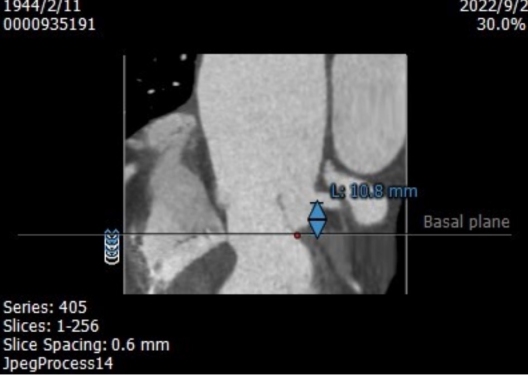

CT评估

左冠高度10.8mm

右冠高度14.1mm

制定策略

患者入路条件良好,三叶式主动脉瓣,主动脉瓣重度反流,流出道较短,STJ、升主动脉较大,瓣膜释放容易位移,瓣下1~2mm起始释放,最终锚定瓣下3mm。